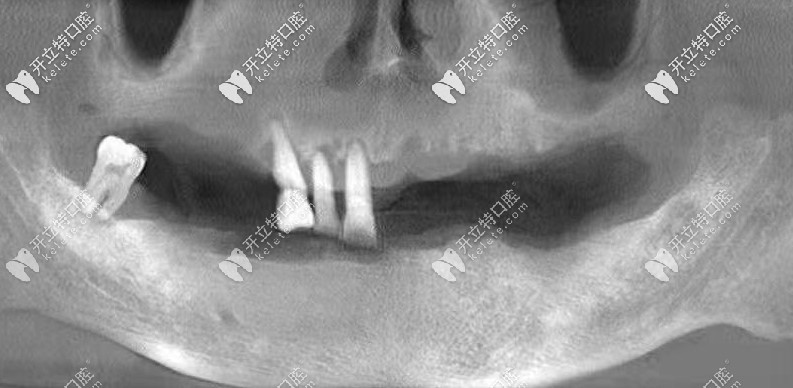

爺爺做全口種植牙后拍的CT↓↓↓

經(jīng)過(guò)檢查發(fā)現(xiàn),爺爺牙槽骨萎縮比較厲害,如果選擇常規(guī)種牙的話,是需要植骨粉骨膜的,花費(fèi)大不少,而且相對(duì)比較痛苦。

所以,醫(yī)生推薦了allon6種植牙技術(shù),這個(gè)不可不用植骨粉骨膜,而且當(dāng)天種牙,戴上臨時(shí)牙冠,回家就可以吃東西了。